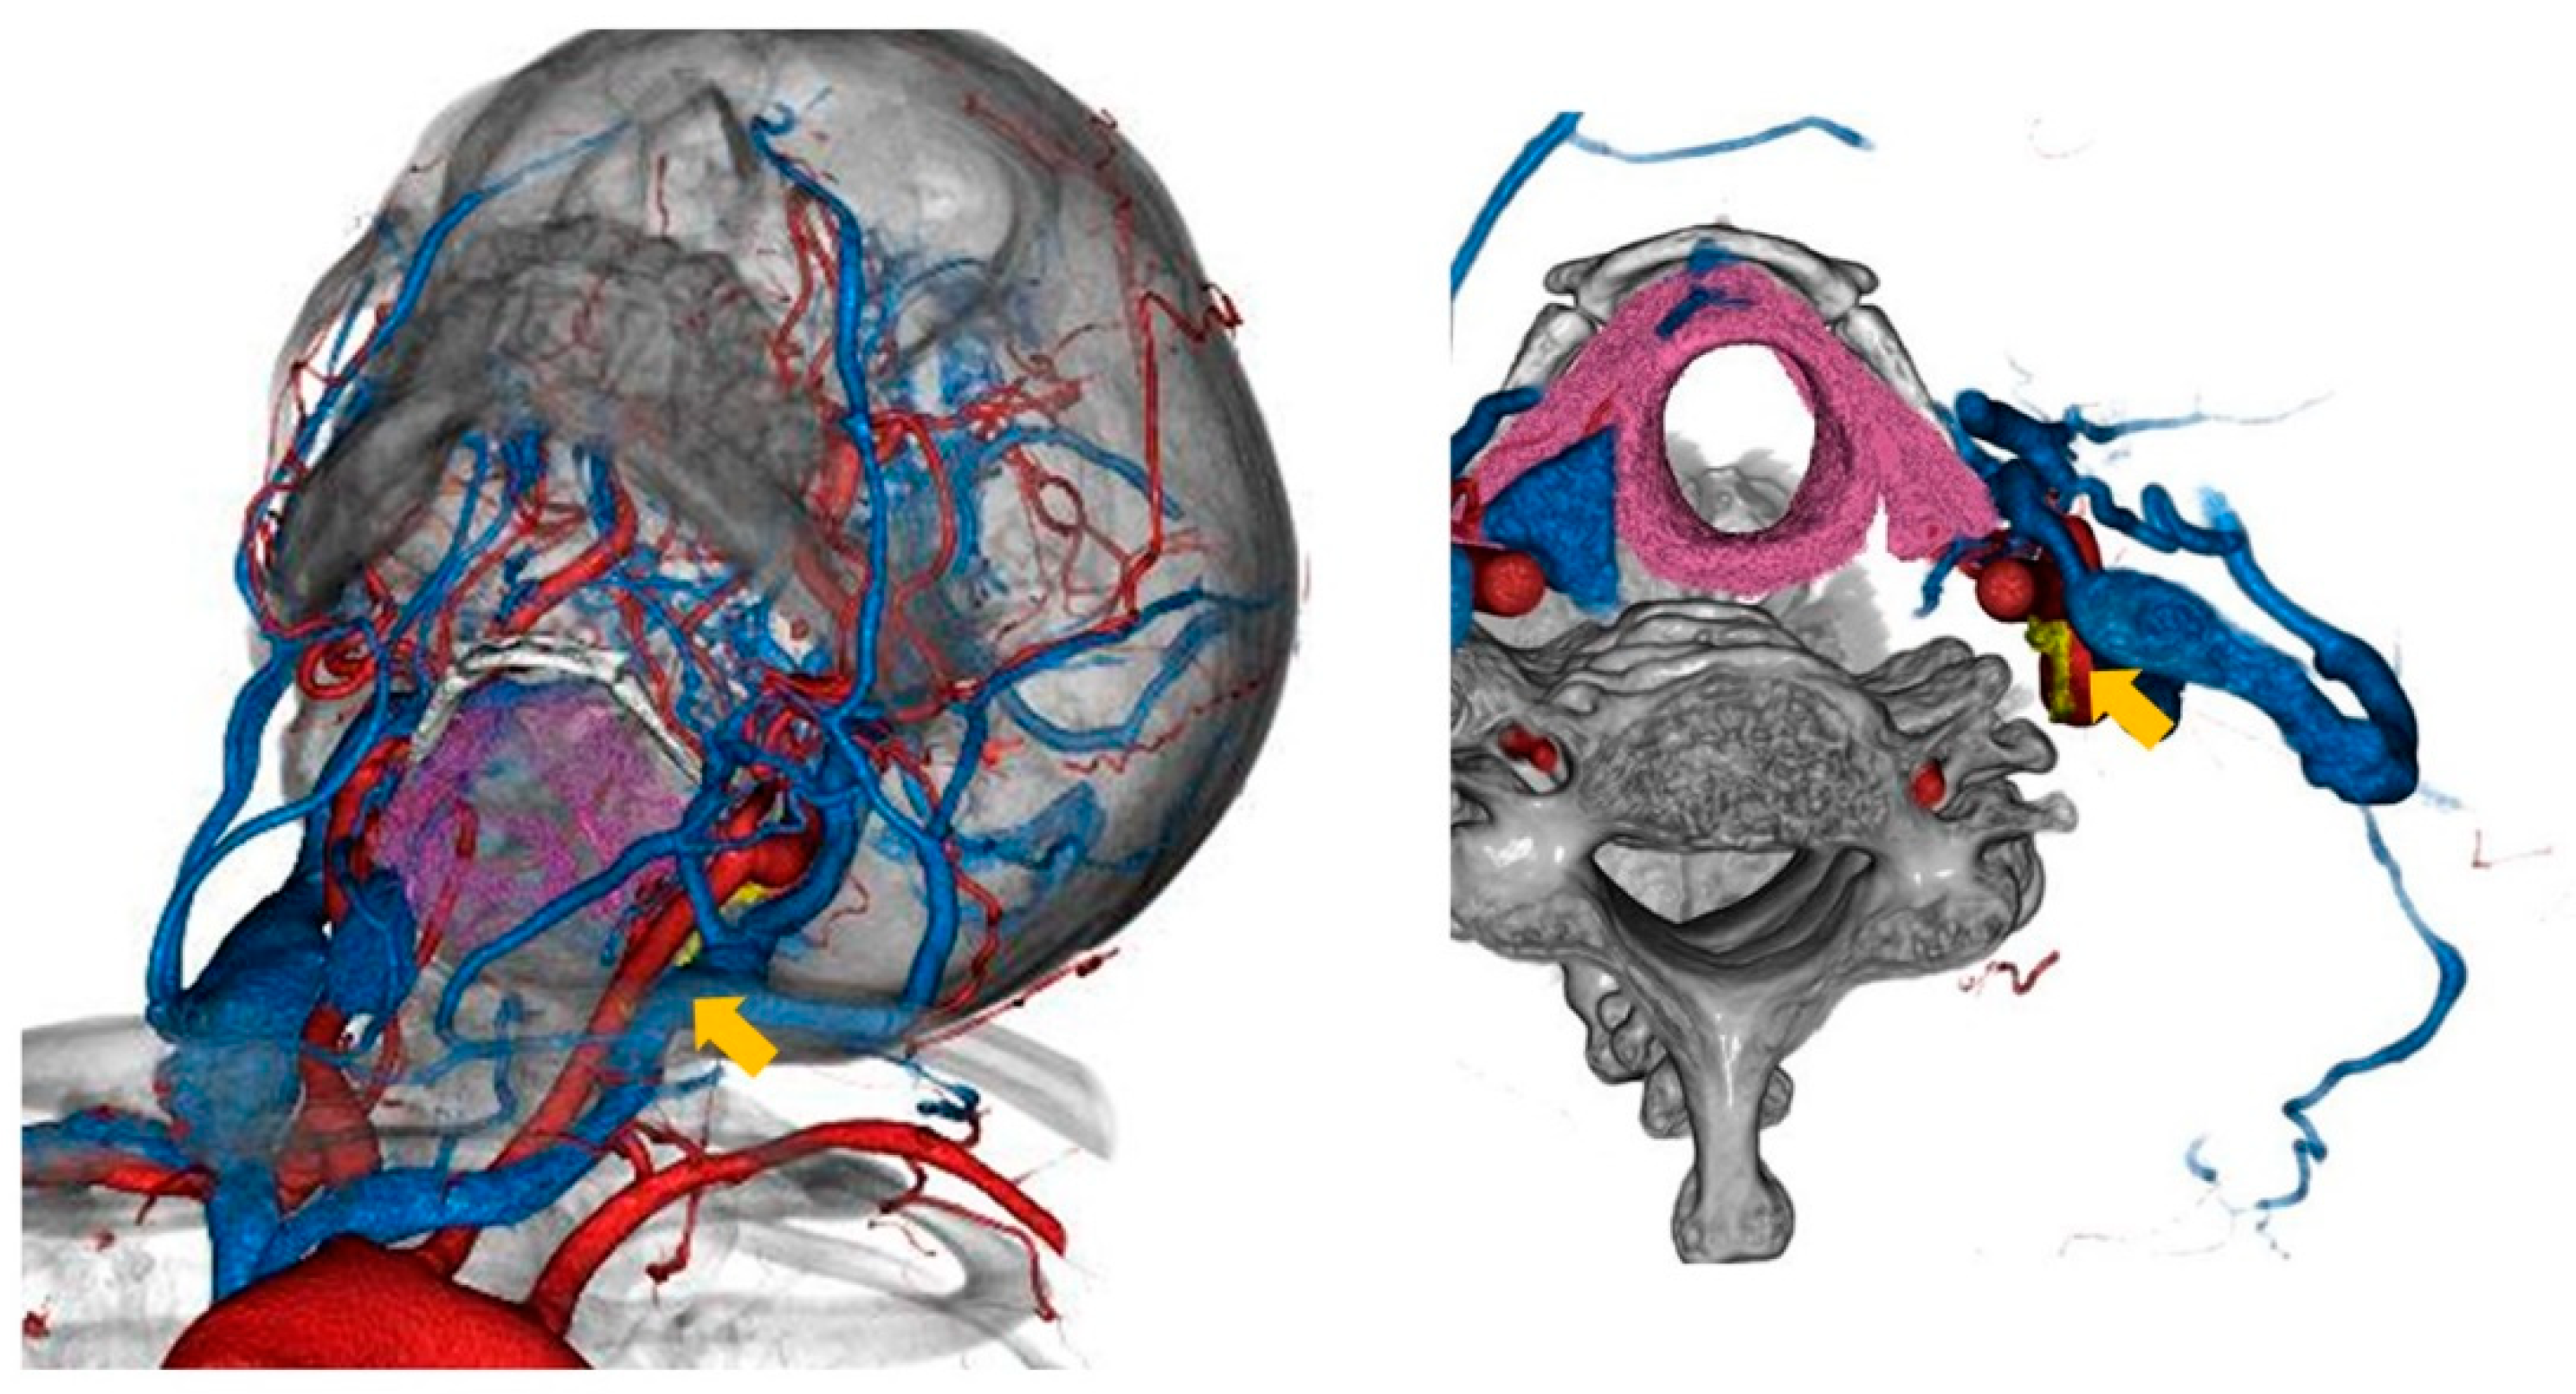

Figure 2.

The visualized vagus nerve and its anatomical relationship with CCA and IJV in case 2. The vagus nerve was colored yellow (arrow).

The vagus nerve was successfully visualized in fusion images in both cases using this method (Figure 1 and Figure 2). Unfortunately, the preoperative fused images could not discriminate the cardiac branch of the vagus nerve from the main trunk of the vagus nerve. The IJV was bifurcated at the cricoid cartilage level according to the images in case 1, and the transverse skin incision was set one finger width below the cricoid cartilage. We preoperatively predicted the vagus nerve detection by pulling the IJV laterally in both cases 1 and 2 based on the preoperative fusion images. Cervical ultrasonography was also performed just after general anesthesia was induced in both cases, and these images were revealed in Figure 3. Accordingly, the location of vagus nerve was identified in case 1, but was unclear in case 2.